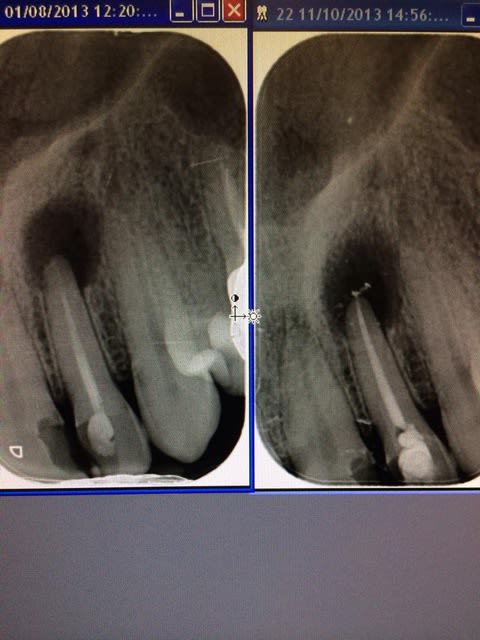

Endo refaite (par moi) , sous digue avec irrigation abondante.

Je viens de revoir la patient , aucune guérison .

J ai obture a l hydroxyde de calcium avant de reobturer .

Pas d evolution en un an .les scans sont au cab .la lesion est tjs identique .

L'endo est belle, la resection apicale a toute les chances de marcher. Et puis au pire je ne vois pas pourquoi ne pas tenter !